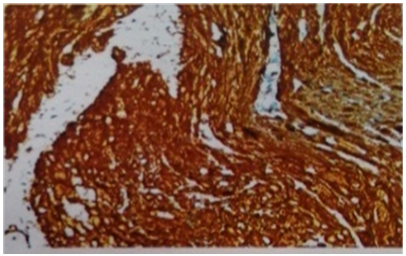

A 53year old lady presented with urgency and frequency for 3months, with two episodes of painless total gross hematuria. She developed acute urinary retention and was catheterized elsewhere and referred to our institute. She had no urological or spine surgeries, no known comorbidities or prior episodes of hematuria. Clinical examination was unremarkable. Ultrasound (US) showed a heterogeneously hypoechoic lesion of 4 x 3 x 4cm in bladder base (Figure 1). Contrast enhanced computed tomogram (CECT) showed a 5 x4 x 4cm well circumscribed hypodense lesion arising from trigone, without hydroureteronephrosis (Figure 2). At cystoscopy, a mucosal bulge measuring around 5 x 5 cm was seen in the right lateral wall extending upto bladder neck and a cecoureterocele was suspected (Figure 3). Transurethral resection (TUR) was done and it showed fragments of tumor tissue composed of spindle cells arranged in sheets and interlacing fascicles, without mitosis or necrosis, suggestive of leiomyoma bladder (Figure 4). Immunohistochemistry showed smooth muscle antigen (SMA) and desmin positivity (Figure 5). Repeat TUR and complete enuceation of the lesion was done. At 6 months of follow up patient is doing well without recurrence or hematuria.

Figure 5 Photomicrograph. Immunohistochemistry showing smooth muscle antigen (SMA) and desmin positivity (40X).